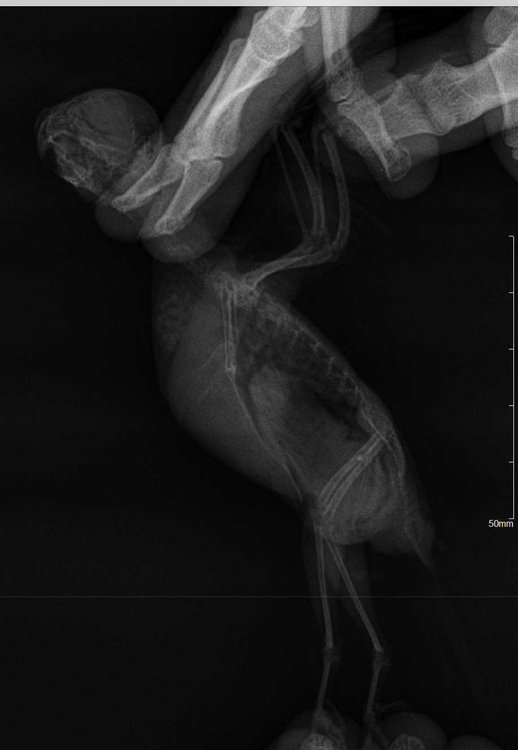

Вчера птиц немного поклевал ночью лакомства. Еду основную не ест. Врач сказала запереть в клетке, чтобы не летал. Заперла - бегает по жердочке туда сюда. Прилагаю фото кала сегоднЯшнего и фото рентгена к сожалению на диске выдали и открыть его невозможно, может кто сможет подсказать?

@Zosia, прочтите, пожалуйста, рентген.